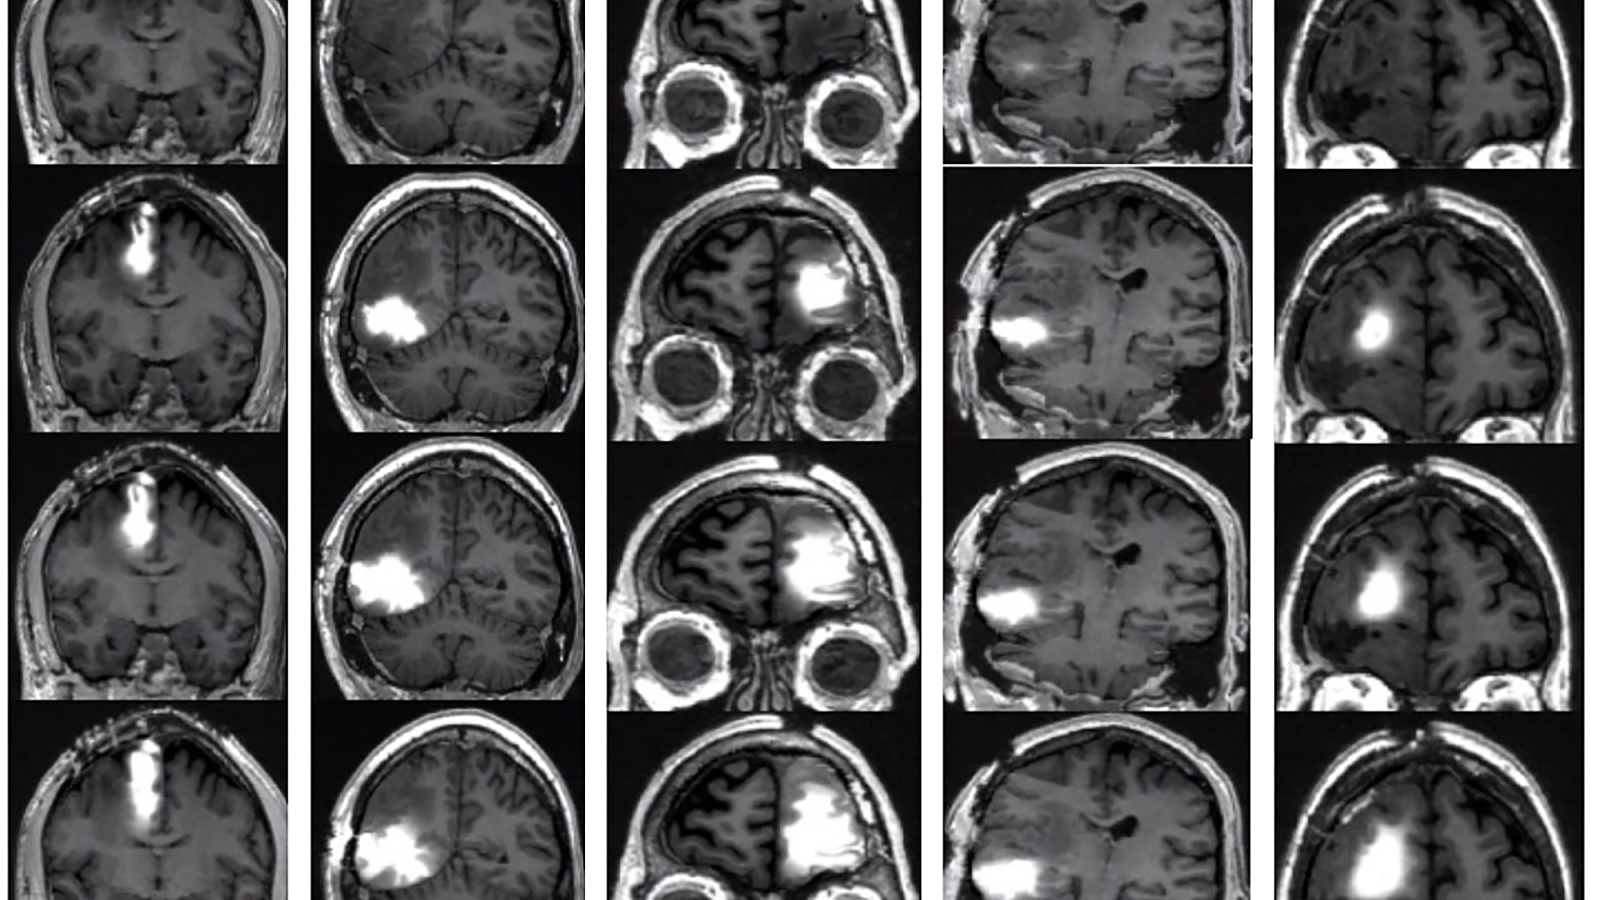

The challenge: The standard treatment for glioblastoma — the most aggressive form of brain cancer — starts with surgery to remove as much of the tumor as possible. After that, patients typically undergo chemotherapy and radiation therapy to kill lingering cancer cells.

But even with treatment, the prognosis for glioblastoma isn’t great — the cancer almost always comes back, and patients live an average of just 12 to 18 months after diagnosis.

The trial: For the trial, more than 300 newly diagnosed glioblastoma patients were treated with either the brain cancer vaccine or a placebo after standard treatment (surgery to remove their tumor, when possible, followed by radiotherapy and chemotherapy).

In the end, 13% of all trial participants treated with DCVax lived for more than five years after diagnosis, compared to 5.7% in the comparison group used for the study, which consisted of more than 1,300 patients from the control groups in other, previous glioblastoma trials.

One trial participant lived for more than 8 years after diagnosis.